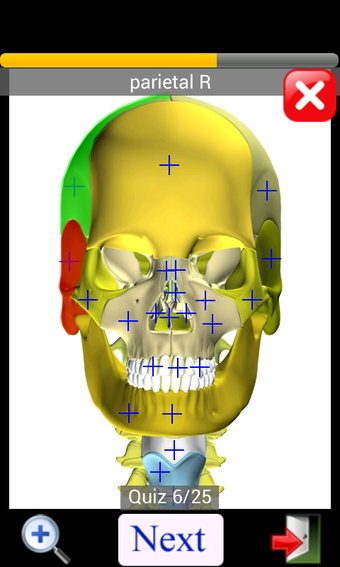

Anatomy Quiz Free es una aplicación de Android de Education Mobile que ofrece una amplia gama de cuestionarios para ayudar a los usuarios a aprender anatomía humana. La aplicación cuenta con más de 500 cuestionarios que ponen a prueba tu capacidad para identificar la ubicación correcta de un objeto dado su nombre. Los cuestionarios se generan a partir de modelos de anatomía 3D virtuales, lo que los hace más atractivos e interactivos. La aplicación es gratuita y no hay versiones premium ni compras dentro de la aplicación.

La aplicación es compatible con los idiomas inglés, francés, español y alemán, lo que la hace accesible para usuarios de diferentes partes del mundo. Las imágenes de alta resolución son nítidas y claras, y la función de zoom con pellizco te permite acercar y alejar las imágenes para una mejor vista. El cuestionario de posición viene con un temporizador, lo que lo hace más desafiante y emocionante. Además, la aplicación tiene una función de transferencia a la tarjeta SD, lo que facilita su transferencia a otros dispositivos.